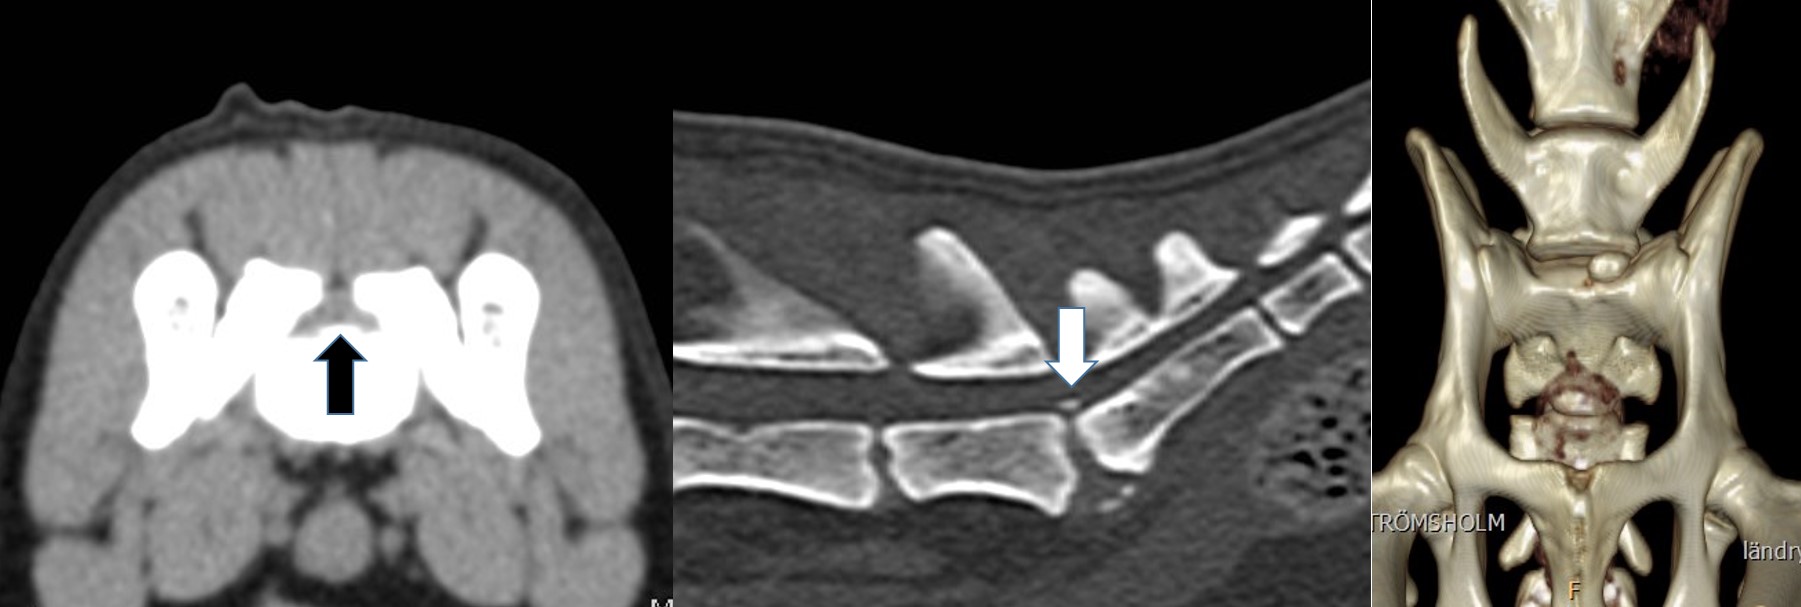

At our hospital we see cat patients after sustaining a trauma. They can have spinal fractures (Fig 1). But because cats have normally a very elastic body, they bend the spine during the trauma until the disk ruptures with a traumatic disk extrusion as consequence. The damage to the spinal cord can be severe, but in most cases a surgery would not help. The MRI is the only diagnostic tool to clearly diagnose such a traumatic extrusion (Fig 2). Fractures to the sacrum and the first vertebra of the tail are also typical for cats. The nerves to the bladder are often damaged in these patients, so the cat has to be in the hospital to ensure the treatment of bladder and fracture (Fig 3).

Fig 1 Fig 2

Fig 1 Fig 2

Middle aged and older cats sometimes change their behavior, they don’t jump up anymore, play less and maybe do not move so much outside. This is often a sign of pain in the hind legs or in the spine. Like German Shepherd Dogs cats can have degenerative lumbo-sacral disease (Fig 4). The life quality of these cat patients can greatly improve with the right pain medication, but the disease should be diagnosed first with a CT examination, because the pain could also come from another place, for example a cruciate ligament rupture. Surgical treatment of lumbo-sacral disease is rarely necessary in cats.

Fig 3: Tail fracture in a cat Fig 4: Lumbo-sacral disease